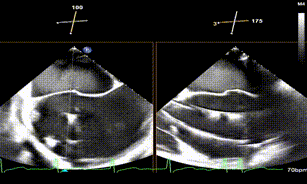

将SW0609型号二尖瓣夹(短宽型)送入左心房后,于2区进行轨迹测试与方向调整,使系统整体靠近病变区域,完成左心房定位,夹臂方向调整至12点钟方位。确认轨迹与方向满意后,充分释放系统张力。在3D-MPR引导下,将系统送入左心室,于2偏3区进行捕捞夹持,可见前后叶Bouncing明显。夹子关紧后,3D超声显示夹子方向良好,组织桥稳定,瓣叶活动受限显著,内侧反流明显减少,外侧仍残留中央型反流。平均跨瓣压差提示未造成瓣膜狭窄。为进一步减少反流,计划在外侧追加植入第二枚SW0609(短宽型)二尖瓣夹。

第一枚夹子跨瓣前定位

第一枚夹子捕捞

第一枚夹子释放前上彩

第一枚夹子释放后血流

第一枚夹子释放后组织桥稳定

第一枚夹子释放后血流3D

第1枚夹子释放后压差